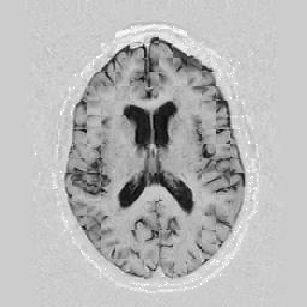

The results are shown for another pair of images in Figure [*].

Figure: Multi-scale NRR. From left to right, top then bottom: before NRR; after 5 iterations of NRR at level 2; after another 5 iterations of NRR at level 1.